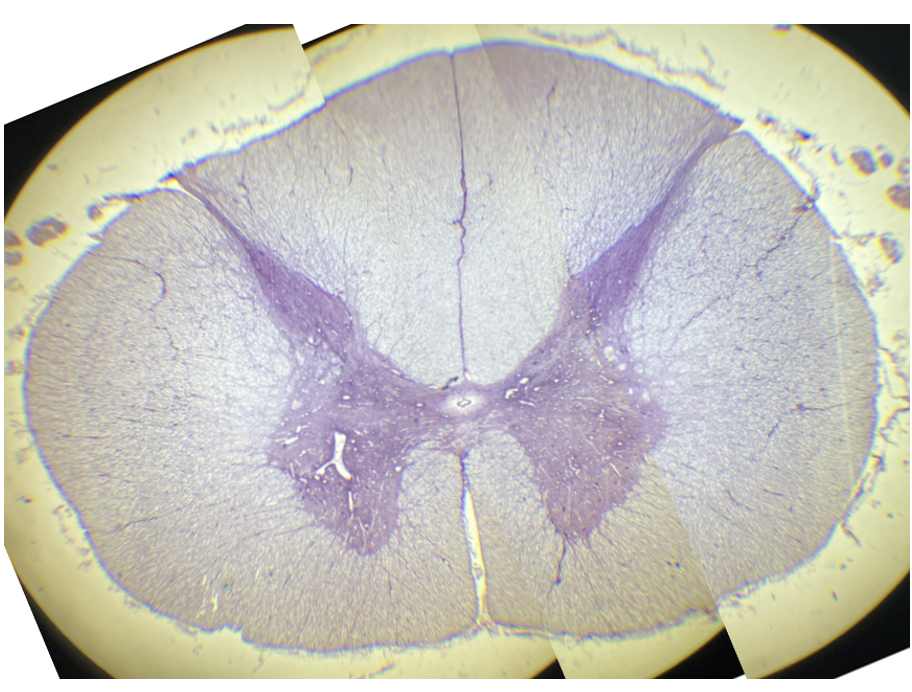

What is this?

Cross section through the spinal cord, showing the ventral horn.

Grey matter of the ventral horn

White matter of the ventral horn